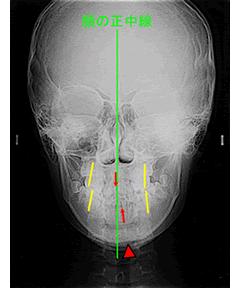

正面セファログラムの赤い矢印が前歯の正中(真ん中)ですが、上顎に比べて下顎の右側が長く、オトガイ(赤い三角印)とともに正中が左側に偏位しています。

正面セファログラムで治療前後を比較すると、上下前歯の正中(赤い矢印)が一致しています。

また、左の下顎臼歯部が上顎臼歯部の内側に収まり、交叉咬合が改善されていることもわかります。